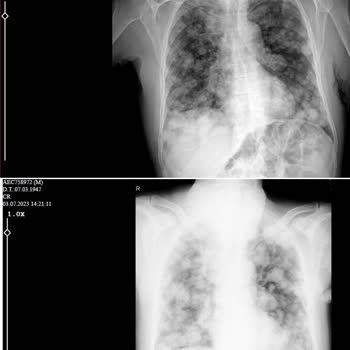

Antalya Eğitim ve Araştırma hastanesinde göğüs cerrahisinde babamı muayene ettirdim. İlaçlı tomografi ve emar sonuçlarında akciğerde 10 cm kitle, böbrek böbrek üstü bezinde de 4 cm'lik kitleler vardı. Dr. Pet çekimi istedi. Sonucuna göre en son akciğerden biyopsi istedi. Ancak biyopsi için bayramda ...